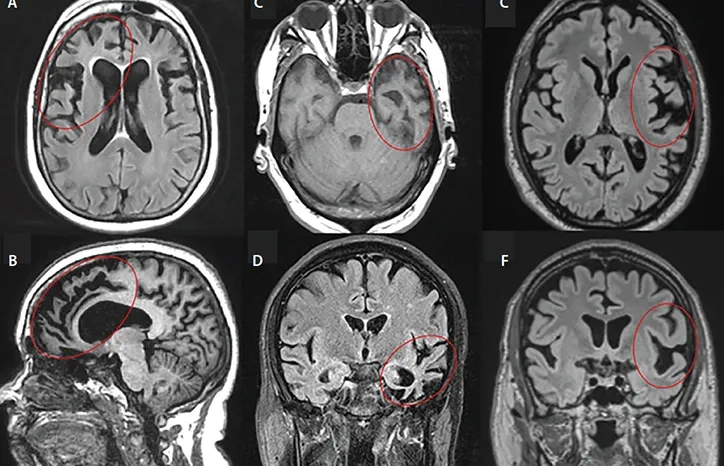

Key differences between FTD vs Alzheimer's